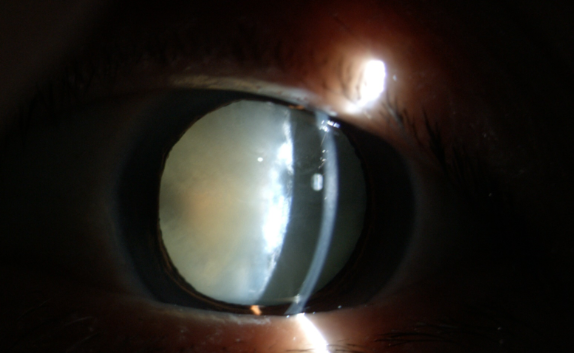

糖尿病為什么更易得白內(nèi)障

在臨床中,很多糖尿病患者不太重視診治,尤其忽視糖尿病導(dǎo)致的多種眼科并發(fā)癥,如白內(nèi)障。糖尿病友得白內(nèi)障較普通人來說有三個(gè)特點(diǎn):

(1)糖尿病患者比一般老年人白內(nèi)障發(fā)生率高;

(2)糖尿病患者比一般老年人白內(nèi)障發(fā)生早;

(3)糖尿病患者比一般老年人白內(nèi)障成熟快。

糖尿病合并白內(nèi)障應(yīng)盡早手術(shù)

糖尿病患者與一般的白內(nèi)障患者不同,因?yàn)樘怯褌兂?huì)伴有糖尿病性視網(wǎng)膜病變和眼部其他損害。醫(yī)生要求每3~6個(gè)月進(jìn)行一次眼科檢查,目的是延緩甚至阻斷糖尿病眼病的發(fā)生和發(fā)展。

白內(nèi)障癥狀

糖尿病患者合并白內(nèi)障盡早手術(shù)的原因:白內(nèi)障發(fā)生后,不但使患者視力產(chǎn)生障礙甚至失明,還直接影響到醫(yī)生對眼底的檢查和治療,因?yàn)闇啙岬木铙w阻斷了進(jìn)出光線。因此,糖友們的白內(nèi)障手術(shù)治療,既能解除視力障礙,還能掃除糖尿病視網(wǎng)膜病變的檢查、治療障礙,所以應(yīng)盡早手術(shù)。